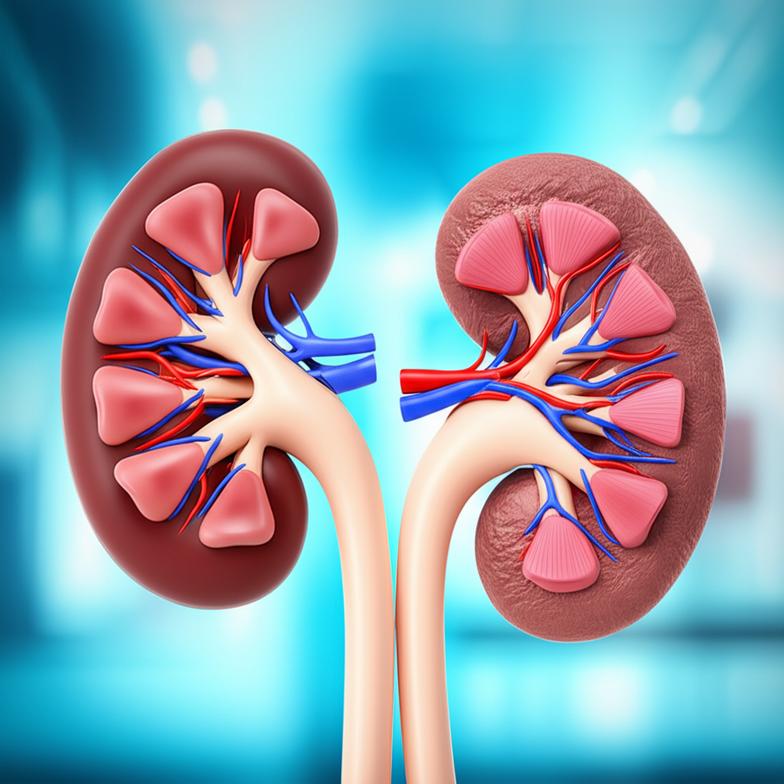

ไตเป็นอวัยวะคู่ที่มีบทบาทสำคัญอย่างยิ่งต่อการดำรงชีวิต ทำหน้าที่มากกว่าแค่การกรองของเสีย ไตยังช่วยรักษาสมดุลน้ำและเกลือแร่ในร่างกาย ควบคุมความดันโลหิต สร้างฮอร์โมนที่เกี่ยวข้องกับการสร้างเม็ดเลือดแดง และช่วยในการควบคุมสมดุลกรด-ด่าง เมื่ออายุมากขึ้น ไตของเราก็เสื่อมสภาพลงตามธรรมชาติ คล้ายกับอวัยวะอื่น ๆ แต่ปัจจัยด้านไลฟ์สไตล์และสิ่งแวดล้อมสามารถเร่งกระบวนการเสื่อมนี้ให้เร็วขึ้นได้